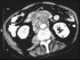

Retroperitoneal rupture of duodenum

Superior mesenteric artery (SMA) syndrome is a gastro-vascular disorder in which the third and final portion of the duodenum is compressed between the abdominal aorta (AA) and the overlying superior mesenteric artery. This rare, potentially life-threatening syndrome is typically caused by an angle of 6°–25° between the AA and the SMA, in comparison to the normal range of 38°–56°, due to a lack of retroperitoneal and visceral fat (mesenteric fat). [Source: Wikipedia ]